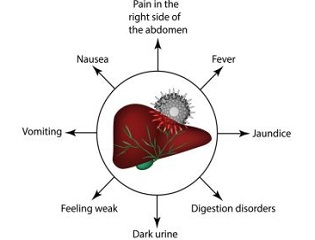

❈ Incidence and Risk Factors

Approximately 1 in 20 people may have gall stones.

About one in three women, and one in six men, form gallstones at some stage in their life.

The risk of forming gallstones increases with pregnancy, obesity, rapid weight loss.

However, they cause no symptoms in two out of three people (Asymptomatic gall stone disease)

❈ Understanding the gallbladder and bile

The gallbladder lies under the liver on the right side of the abdomen. It is a ‘reservoir’ which stores bile. The gallbladder empties the stored bile through the main bile duct into the duodenum.

Bile helps to digest food, particularly fatty foods

❈ What are gallstones?

There may be multiple small stones or a single large stone.

❈ What problems can gallstones cause?

Gallstones are often found when the abdomen is scanned for other reasons.

- Biliary colic: This is a severe pain in the upper abdomen.

- Inflammation of the gallbladder: This is called cholecystitis. This can lead to infection in the gallbladder. Symptoms usually develop quickly and include abdominal pain, high temperature (fever), and being generally unwell.

- Jaundice: It occurs if a gallstone gets stuck in the bile duct. Bile then cannot pass into the gut and hence causes jaundice

- Pancreatitis: This is an inflammation of the pancreas.